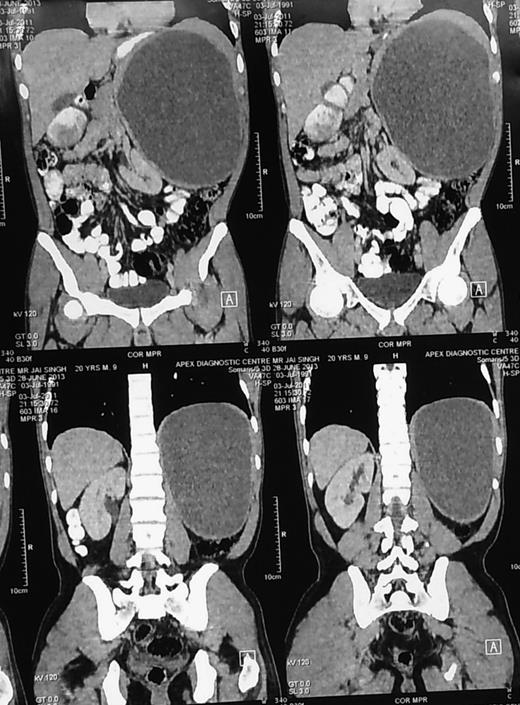

A 47-year-old female presented with complaints of a small lump (Figs 1–5) in left upper abdomen and a past history of fall on ladders a year back. On examination, there was a small lump confined to the left hypochondrium, firm in consistency with rounded borders suggesting origin from the spleen. The patient underwent CT scan of the abdomen after abdomen sonography and CECT suggested the presence of a cystic lesion originating from the lower margin of spleen ∼12 × 8 cm in size. The patient underwent a surgery and cystic lesion was removed preserving the spleen (Figs 6–8). The cyst on histopathological examination was a pseudocyst.

CECT abdomen showing huge splenic mass compressing surrounding structures.